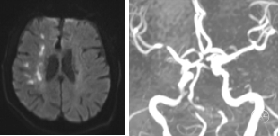

4月13日CT平扫:脑内多发腔隙灶及缺血性白质病变。ASPECT:9分。

4月13日CTA:右侧大脑中动脉闭塞。

右侧颈总动脉正侧位:右侧大脑中动脉M1闭塞,右侧大脑前动脉未见显影,右侧胚胎型大脑后动脉显影正常。

左侧颈总动脉正侧位:前交通开放,双侧大脑前动脉由左侧颈内动脉供血,右侧大脑前动脉通过软膜支向右侧大脑中动脉供血区部分代偿,左侧胚胎型大脑后动脉显影正常。

左侧椎动脉正侧位:基底动脉、双侧小脑上动脉纤细。

4月16日复查核磁MRI+MRA:右侧半卵圆中心、右侧额颞顶枕叶多发急性期脑梗死;右侧大脑中动脉M1段重度狭窄,左侧椎动脉闭塞。计划继续内科药物治疗,进行临床、影像随访,评估择期手术适应症。